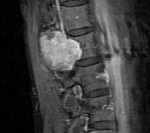

Однако наиболее достоверным методом, визуализирующим экстрамедуллярные опухоли является магнитно-резонансная томография. Она дает возможность определить точное расположение, распространенность, форму опухоли, предположить ее вид, оценить степень спинальной компрессии. При наличии противопоказаний к МРТ альтернативным методом выступает КТ-миелография. При опухолях сосудистого генеза дополнительно назначается спинальная ангиография. Точно судить о доброкачественности опухоли и ее виде позволяет гистологическое исследование её тканей, забор которых, как правило, производится интраоперационно.